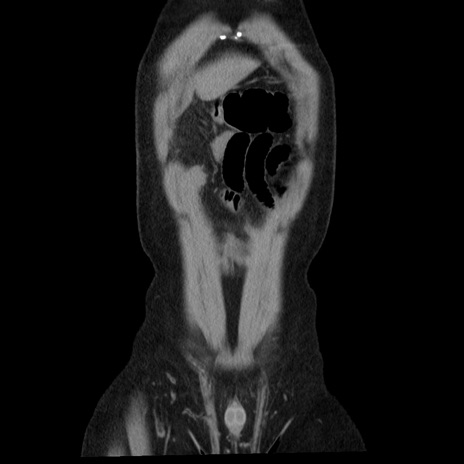

症例29(冠状断像)

【症例】40歳代男性

【現病歴】2日前から胃痛あり。徐々に周期的な激痛に変化した。本日になっても激痛があるため受診。

【身体所見】意識清明、BT 38-39℃台あり、腹部:膨満、やや硬、右下腹部に圧痛あり。

【データ】WBC 8500、CRP 23.26